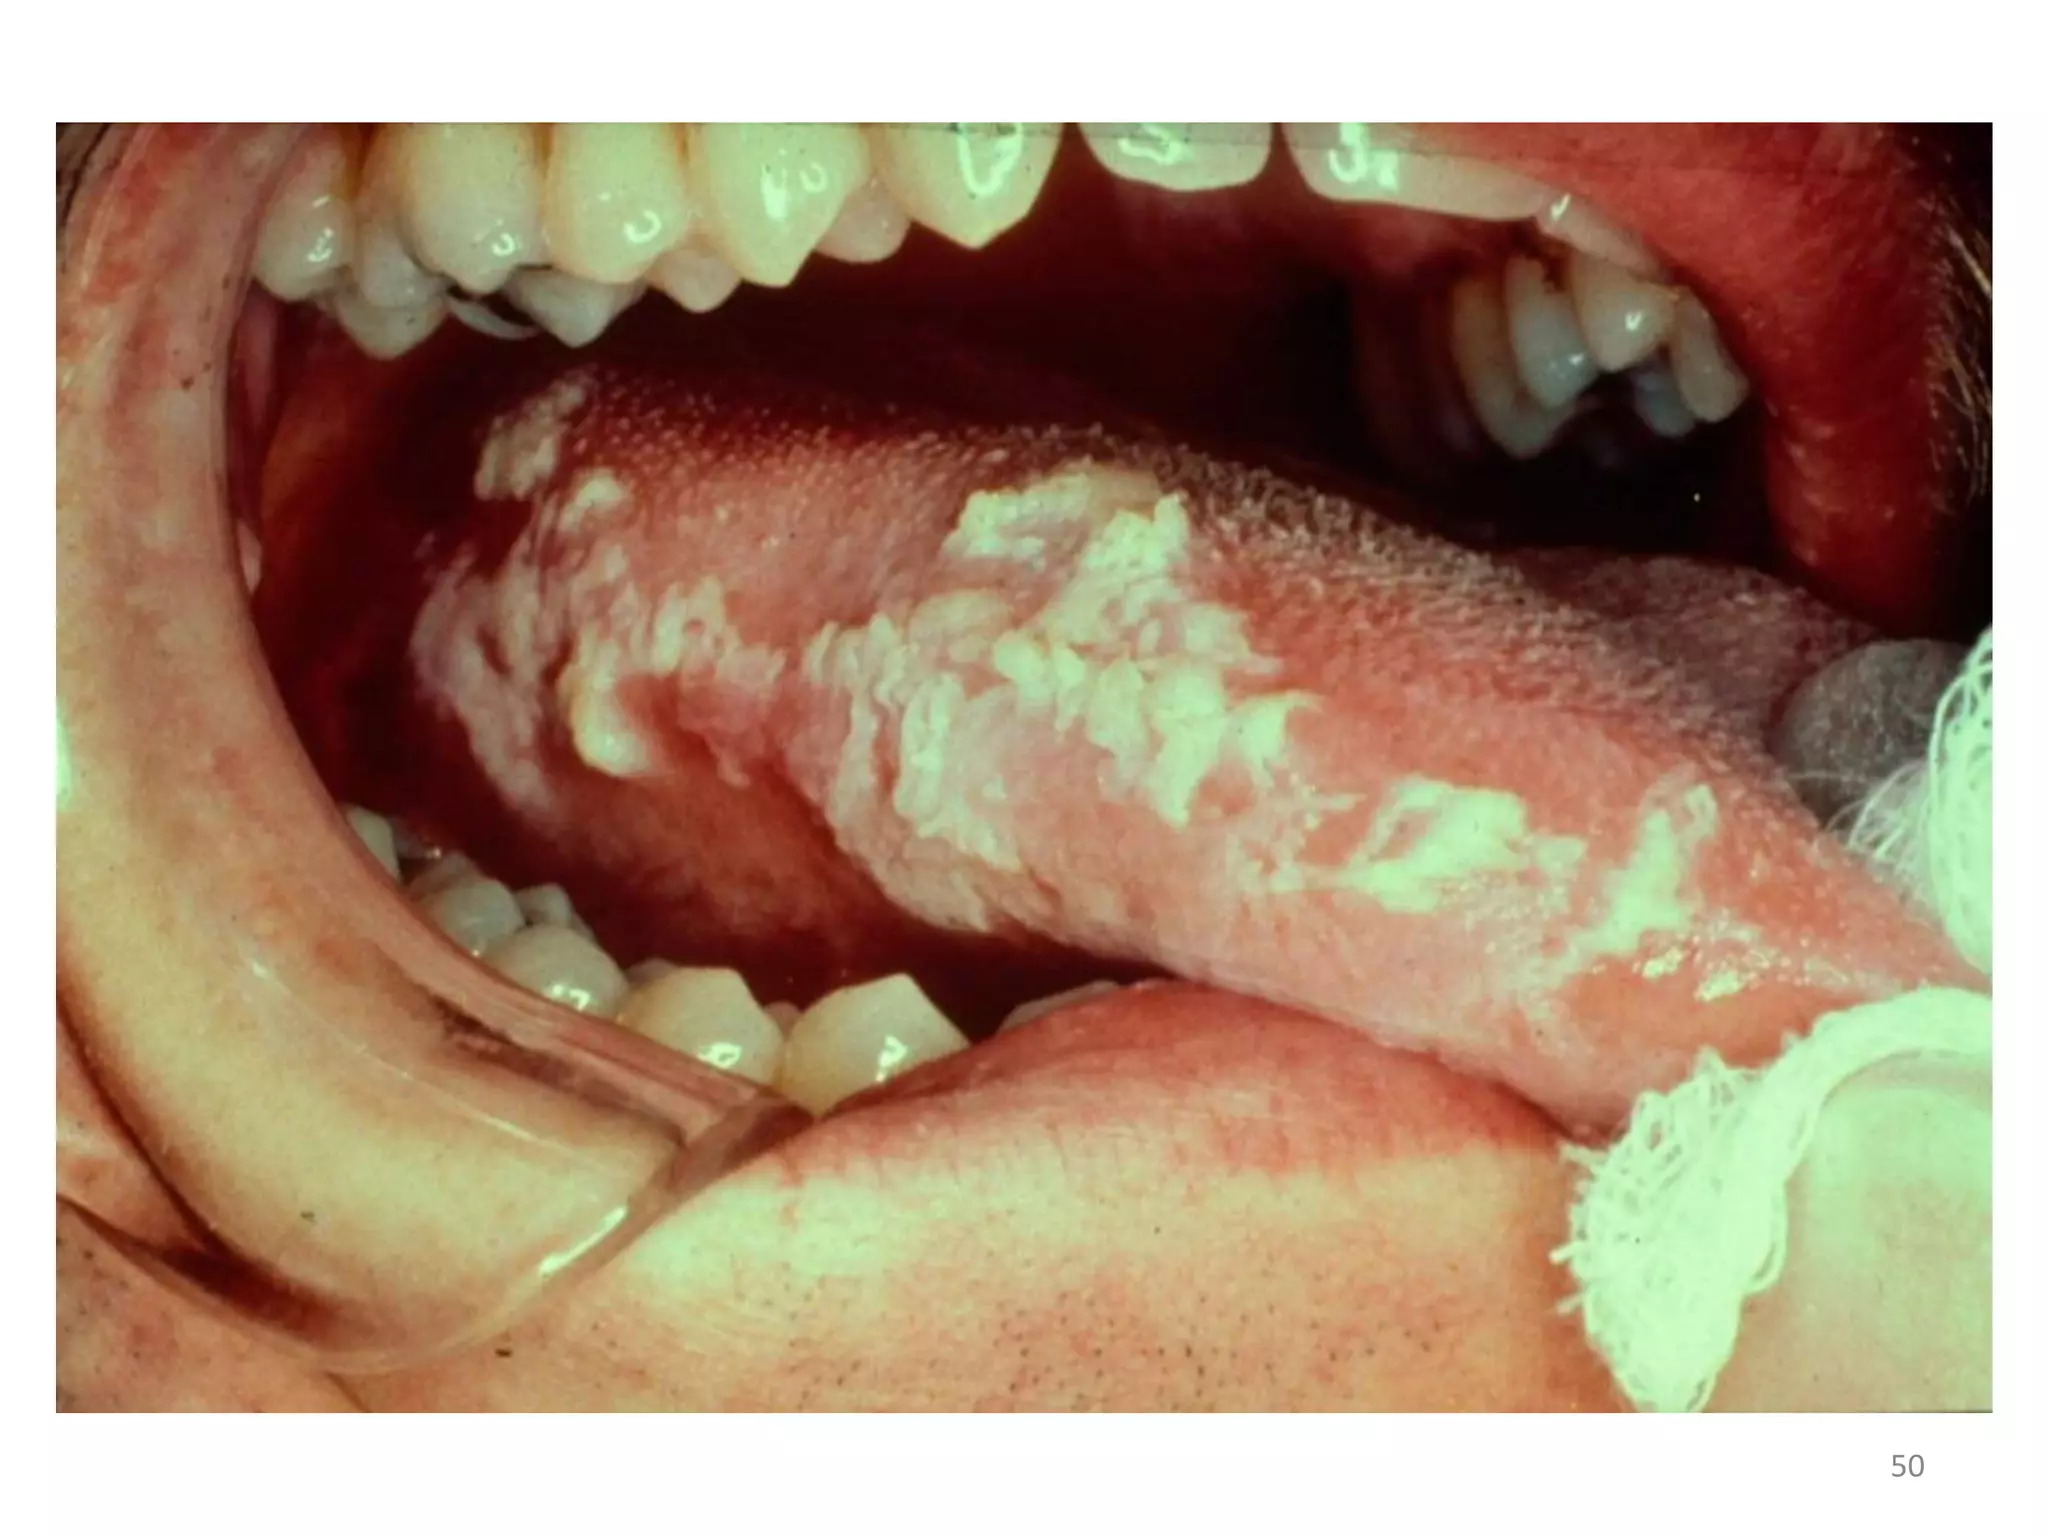

ORAL HAIRY LEUCOPLAKIA:

• Appears as white plaques running vertically on

the sides of the tongue.

• EBV is implicated as the causative factor.

• Usually asymptomatic and doesn’t require any

treatment.

49

50

ORAL HAIRY LEUCOPLAKIA: • Appears as white plaques running vertically on the sides of the tongue. • EBV is implicated as the causative factor. • Usually asymptomatic and doesn’t require any treatment. 49

• #51 white plaques running vertically on the sides of the tongue.